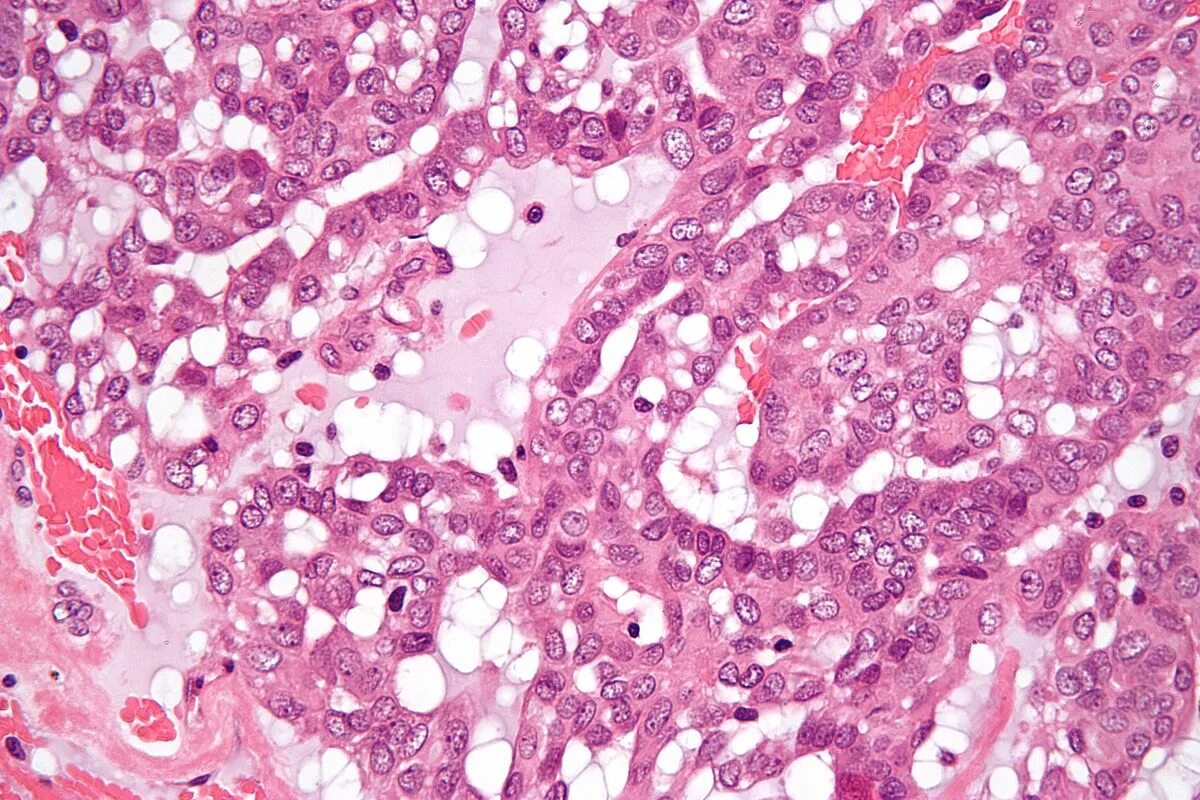

Гистология аденокарциномы